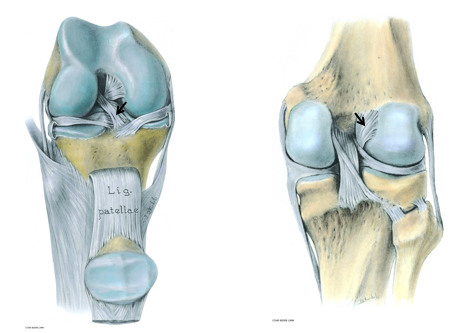

• Menisci

Wedges of fibrocartilage

Deepen articular surface

Shock absorption

Medial Meniscus

•C-shaped

•Broad posteriorly

•Firmly attached to TCL

Lateral Meniscus

•Circular

•Freely moveable

•Attachment for popliteus